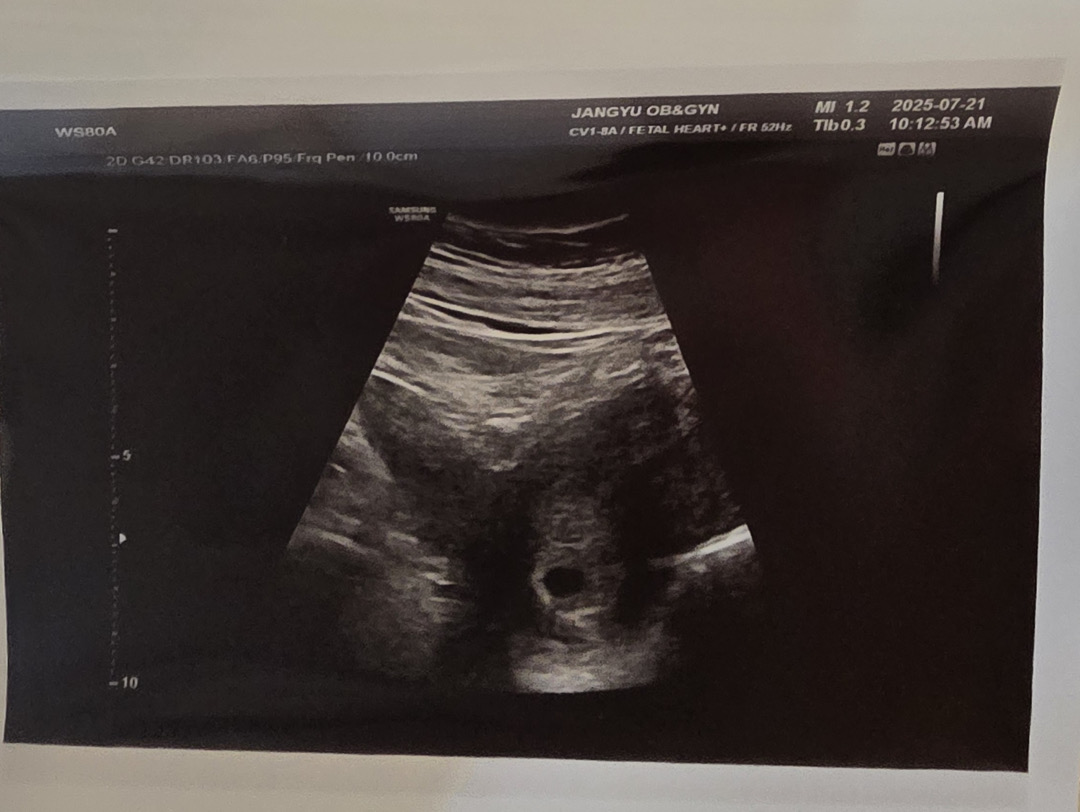

임테기 시약선보다 진해진거 확인하고 7.21에 동그랗게 0.8 cm 집들이 했는데 난황이없어 당황했어요.. 자연임신이라 늦을수도있단 말을 많이 보긴했는데 주수에비해 진도가 없는것같아 매일 불안해요 입덧도 없고 피곤하기만하네요 ㅠㅠ 이제 다음주 금요일에 갈예정인데 난황 늦게보신분 계실까요?